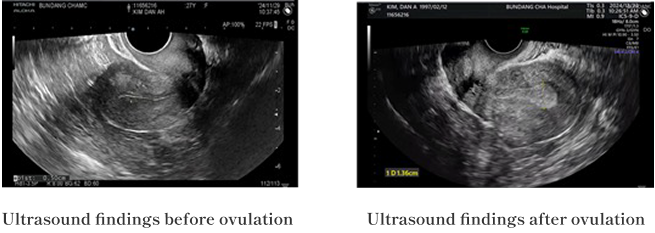

一方で、先進国を含む多くの国々では、幹細胞や上清液エクソソームを併用した不妊治療の臨床が進められており、静脈注射や卵巣への直接投与によって、卵巣の機能を促進し、妊娠率を高める研究が行われています。

実際に、当IVF医療チームが早期閉経不全症(POI)患者に対して臨床治療を行った結果、33%の妊娠効果が確認されました。

韓国CHA病院での臨床治療結果によると

6名中2名の患者において、臍帯由来幹細胞を1回静脈投与した後、18〜24週間で臨床的な改善効果が認められました。

| S001 | 28歳、6年間無月経 |

|---|---|

| 治療後 |

FSHホルモン減少、E2増加傾向

|

| S003 | 36歳4年間無月経 |

|---|---|

| 治療後 |

E2ホルモン増加

|